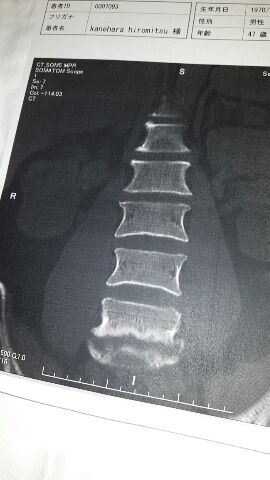

化膿性脊椎炎

俺の一番下の腰の骨、それと仙骨と写真では写ってないけど椎間板、こんなに溶けてしまった。

こんだけ溶ければそりゃあ痛いよな〜。

骨は元には戻らないが、固まって安定すれば大丈夫らしい。

俺はまた運動ができるようになるのかなぁ。

不安だなぁ。

背もちょっと縮んじゃったなぁ。

化膿性脊椎炎、恐ろしい病気だな。